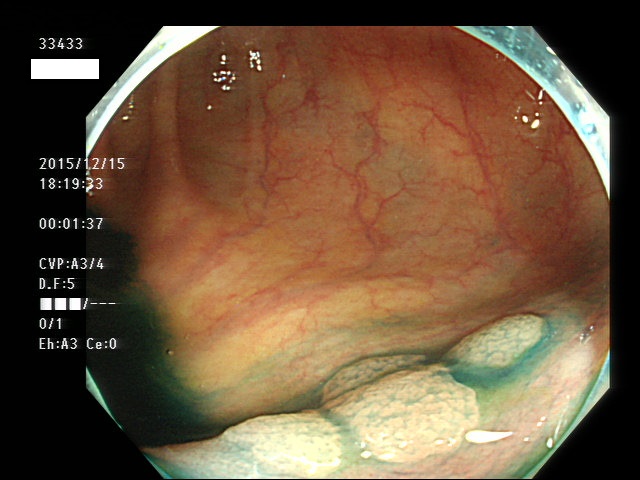

上記100名より抽出した平坦・陥凹型腺腫(=癌化の危険が高いが見落としやすい病変)の内視鏡写真